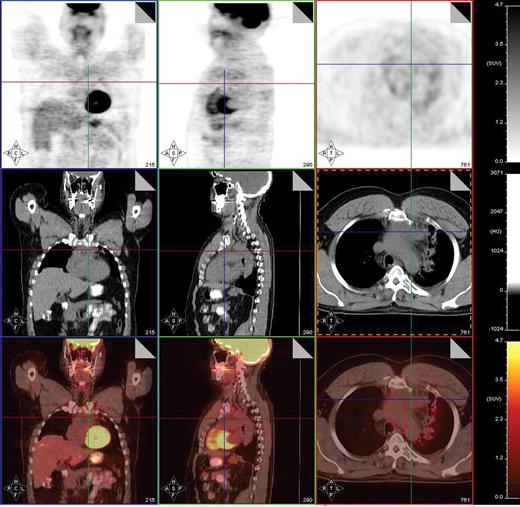

Post-treatment PET/CT scan in a 20-year-old patient with Hodgkin lymphoma showing thymic hyperplasia with otherwise no PET evidence of disease.

Post-treatment PET/CT scan performed 2 months after treatment with 8 cycles of AVD followed by involved field radiation therapy in a patient with stage IIA mixed cellularity Hodgkin lymphoma showing a PET-negative residual mass in the mediastinum measuring 4.2 × 2.9 cm. PET/CT was otherwise negative. This patient is currently without evidence of disease after 23 months of follow-up post therapy.